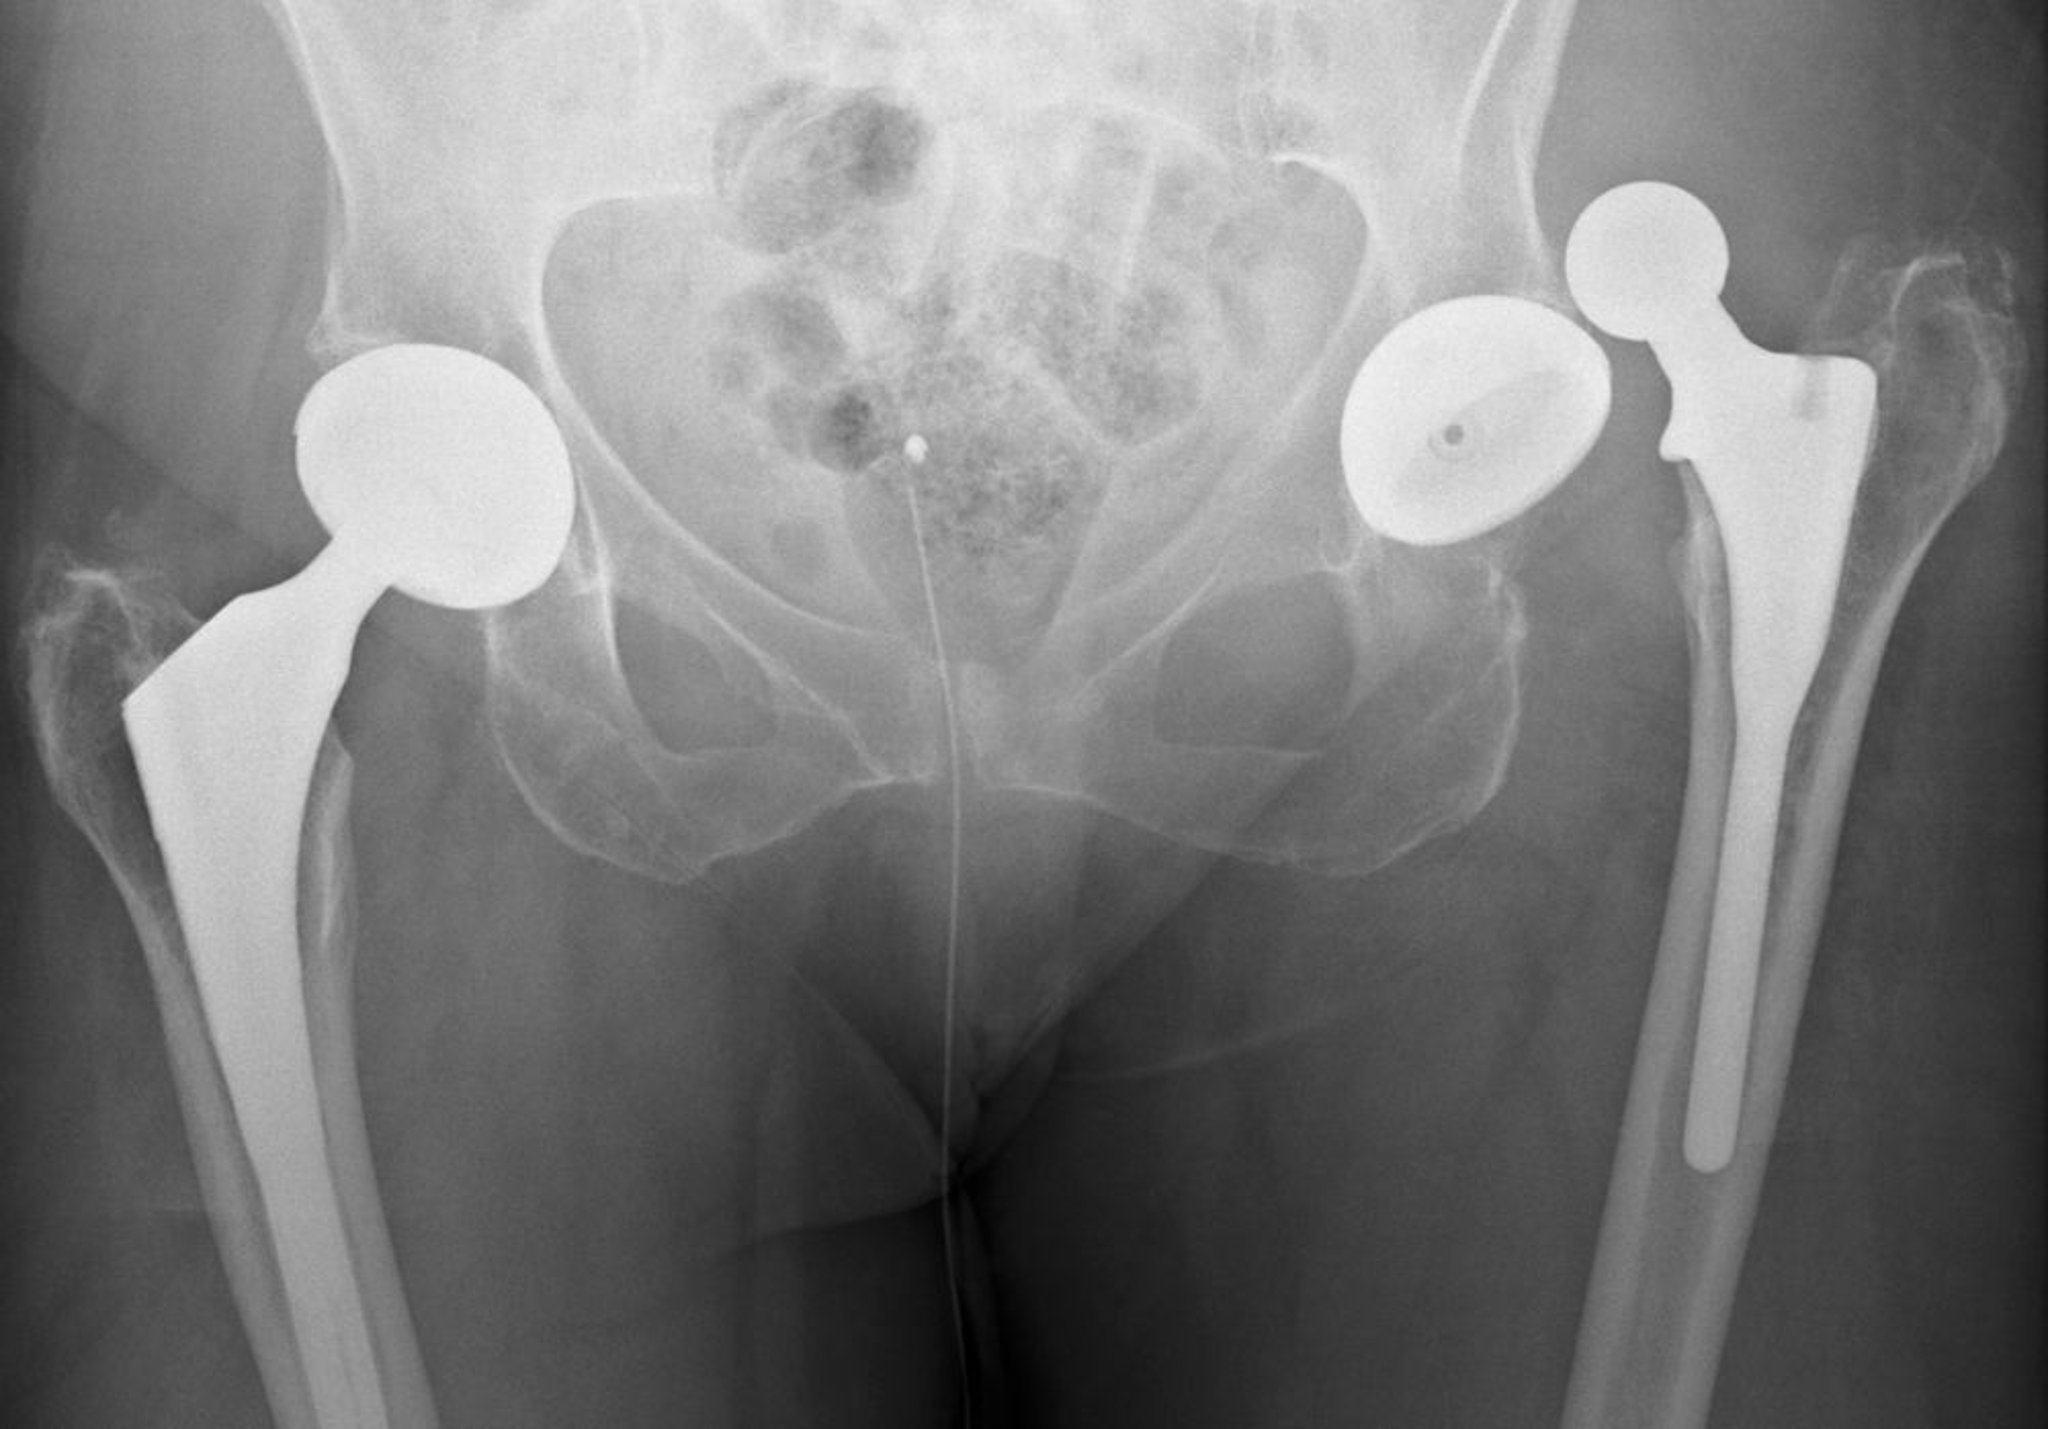

Deslocamento da prótese de quadril

Esse luxação é posterior.